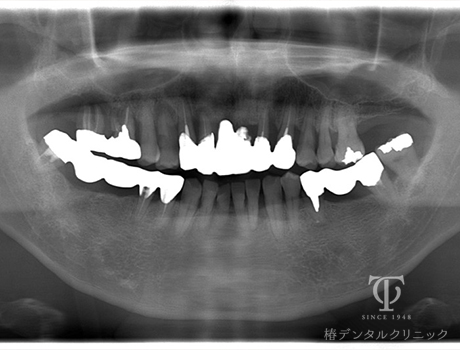

術前レントゲン

-

- 症状

- 右上の痛み

- 治療期間

- 約1年半

- 治療費用

- (上顎)インプラント治療:473,000円×2

(上顎)AGCテレスコープ義歯:1,500,000円

(下顎)インプラント治療:473,000円×2

右上の歯が痛いということで来院されました。インプラントとAGCテレスコープという方法でかみ合わせを再構築しました。